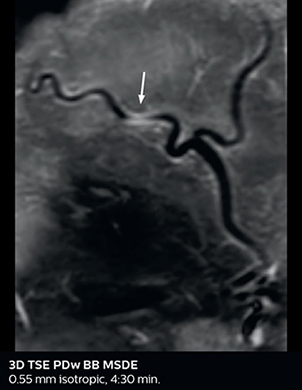

Giant cell arteritis

The 3D TSE T1w black blood MSDE sequence with fat suppression has an isotropic 0.8 mm voxel size and sagittal oblique and axial reformats are made. The images show superficial temporal artery thickening and peri-arterial fat infiltration. The 3D TSE PDw black blood MSDE with fat suppression has 0.55 mm isotropic voxels. The images shows focal involvement of the frontal branch of the superficial temporal artery.

3D TSE T1w BB MSDE

3D TSE PDw BB MSDE

So, what is the actual impact of having more information and more diagnostic confidence? According to Dr. Savatovsky, “One of the indications I’ve seen where using Elition is most impactful is in patients with suspected giant cell arteritis. As an ophthalmologic hospital, we see many patients with suspected giant cell arteritis. Usually we were performing MRI to help us rule out an ischemic stroke, and to verify that the supra aortic vessels are undamaged. With Elition, we still do this, but now we can add on more detailed high-resolution black-blood sequences on superficial arteries. This provides us with high confidence levels for diagnosis of giant cell arteritis (GCA) and as a result, some patients are not sent for a biopsy anymore. A patient who has a normal MRI will not require a biopsy and can be discharged from the hospital in the same day. Before, such a patient would have to stay for about a week, just to find that their biopsy results were negative. We have at least three or four patients a week with suspected giant cell arteritis. For a great deal of these patients we can have a direct impact on their hospital stay.”